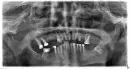

Мне необходимо сделать протезирование всех зубов — сверху и внизу.

Они очень стерлись, но запломбированы, не болят и, не шатаются. При этом отсутствуют по 2 жевательных зуба (внизу и сверху).

Ранее я уже консультировался в клинике, где все очень качественно, но крайне дорого. И мне объяснили, что надо обточить все зубы и поставить имплантанты на месте отсутствующих жевательных зубов, а также удалить 18-й зуб, который будет мешать прикусу.

- Каковы реальные сроки такого протезирования? Клиника, с которой я ранее консультировался, все делает за один прием и отводит 4-5 дней на протезирование всех зубов, а работа с имплантантами (их насчитали в моем случае 8) окончательно завершится через 3 месяца после повторного визита и установки на них коронок.

Прикрепленые фото